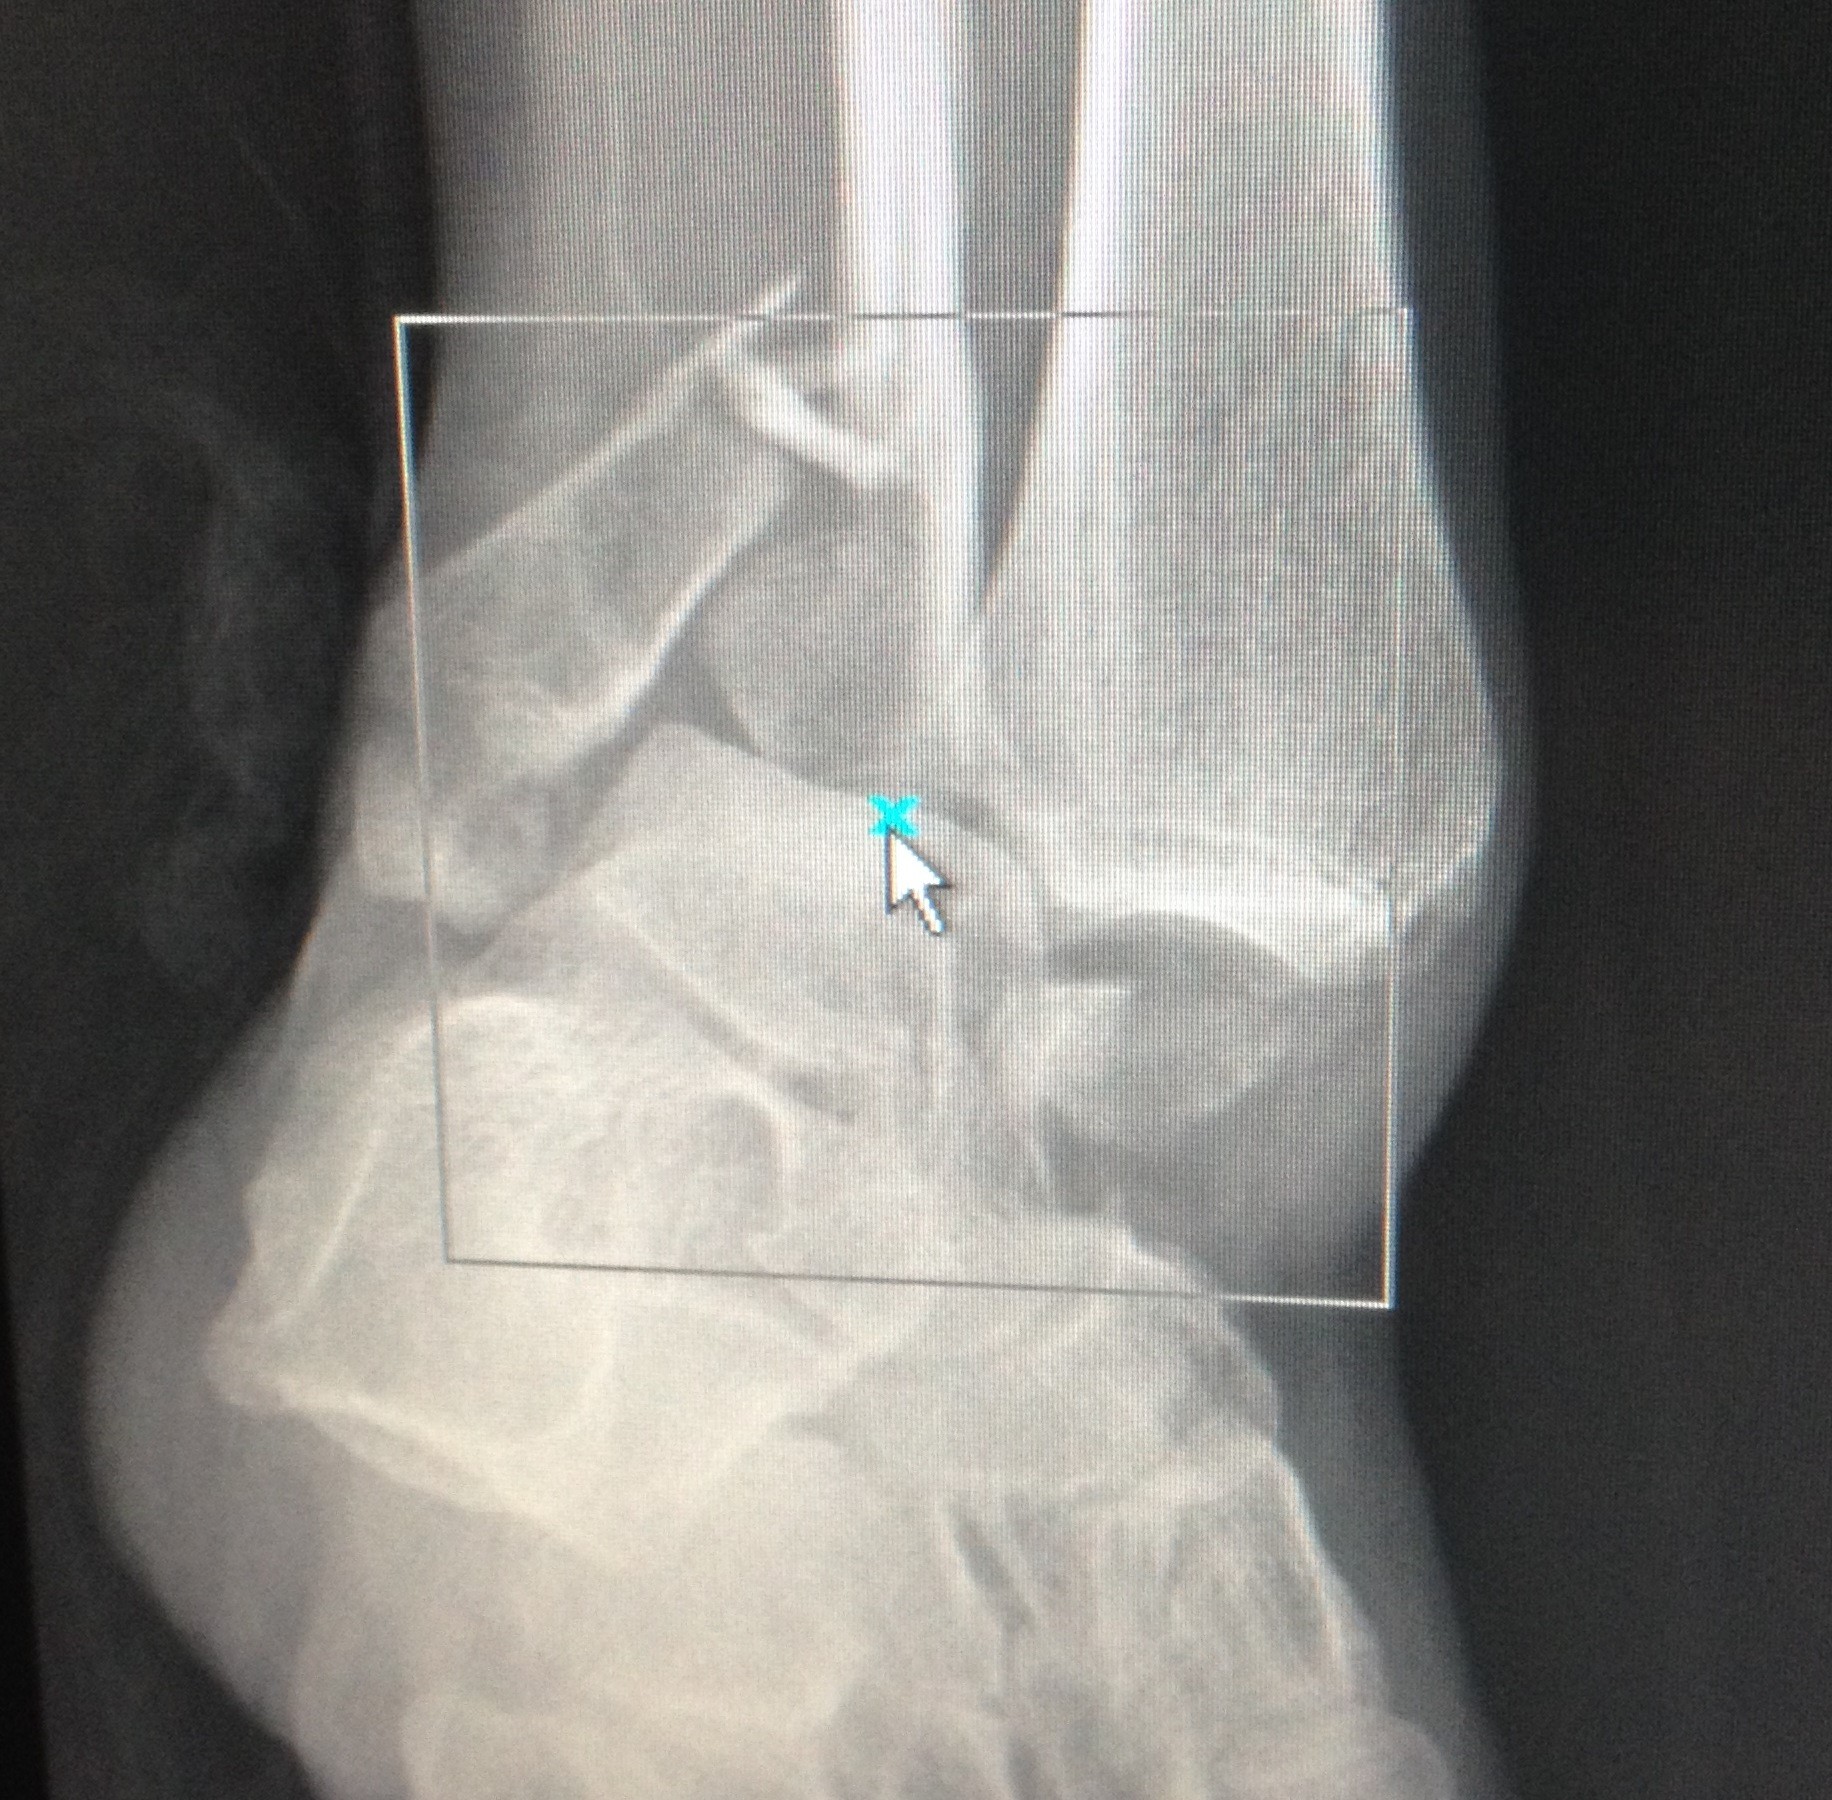

One day was a day like any other here at “the Bird.” This was the x-ray that popped up on a patient before I had the chance to meet her face-to-face:

***SPOILER: the bones aren’t exactly in the right place***

I slid the curtain back and gave her an empathetic look. She already knew I had some bad news– she could tell from the golf-ball sized lump on her ankle where a bone was obviously trying to push its way through her skin. I asked the nurse if she had received any pain medication, because she was remarkably peaceful and gave me a calm smile as I approached her bedside. The patient quickly replied, “I don’t need any medicine”. After a brief discussion about how a reduction procedure works, she hesitantly accepted a dose of morphine prior to sedation.